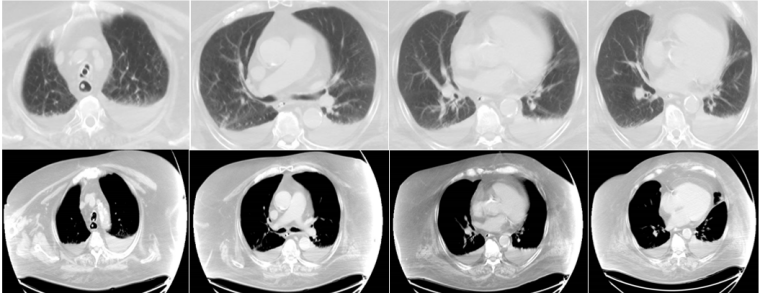

6月14日复查胸部CT,可见患者双下肺膨胀不全(图12)

图片

图12  复查胸部CT(6月14日)